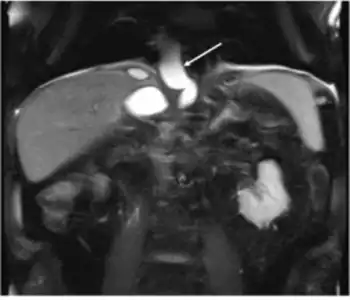

_(1).png)

The most common and effective method of diagnosing a pancreatic pseudocyst is with a CT scan. A pseudocyst generally appears as a fluid-filled mass. In some instances, other methods must be used to distinguish between a normal cyst and a pseudocyst.[3] This is usually accomplished with endoscopic ultrasound or with fine needle aspiration.[2]